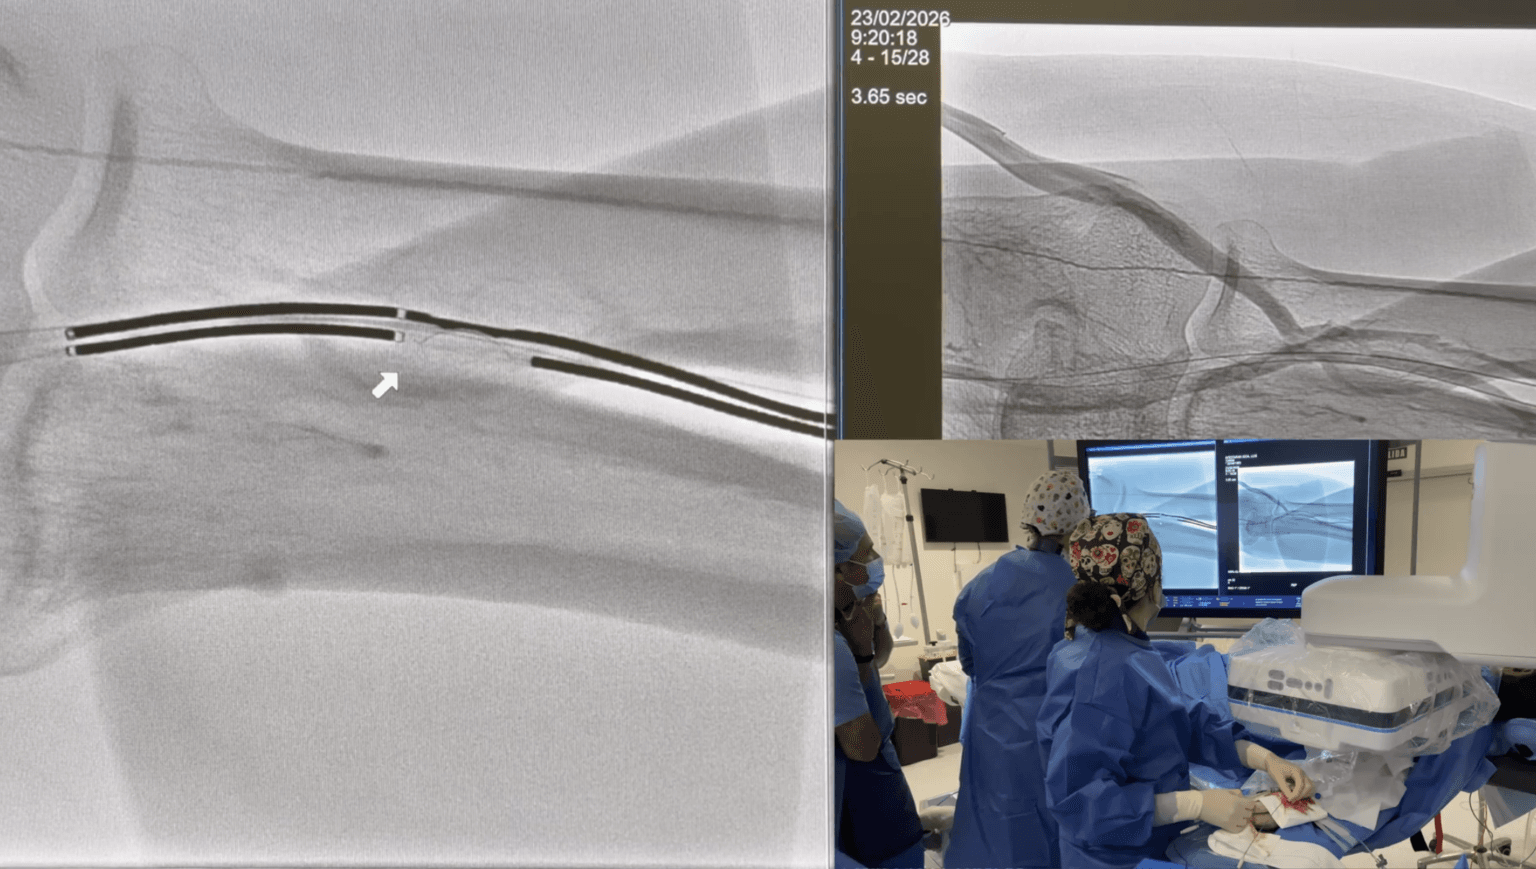

Embolización de varices pélvicas

El Dr. Andrés Guirola realiza embolización de varices pélvicas mediante cateterización de la vena gonadal.